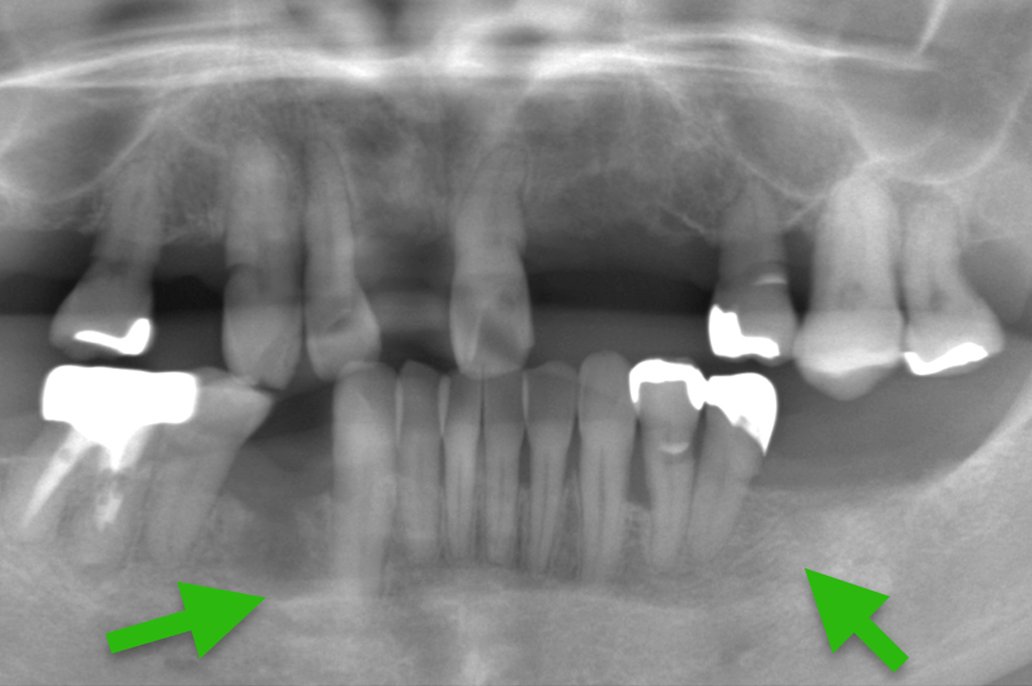

| 主 訴 | 歯がない部分を治療したい |

|---|---|

| 治療期間 | 約4ヶ月 |

| 治療費 | 合計836,000円(税込) |

| 治療内容 | 治療1回目 CT撮影にて顎の骨にインプラントが入ることを確認し、サージカルガイドの型取り 治療2回目 インプラントを入れる治療 治療3回目 縫合してある糸をとり、周りをクリーニング 治療4回目 インプラントに土台を立てる治療 治療5回目 上部構造(被せ物)の型取り 治療6回目 上部構造(被せ物)をセット |

| 治療のリスク | インプラントの手術の後は腫れ、 痛みが出ることがあります。 インプラントの上部構造のセラミックは 稀に欠けることがあります。 |